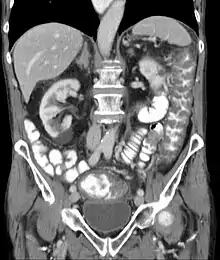

The use of systemic antibiotics, including broad-spectrum penicillins/cephalosporins, fluoroquinolones, and clindamycin, causes the normal microbiota of the bowel to be altered. In particular, when the antibiotic kills off other competing bacteria in the intestine, any bacteria remaining will have less competition for space and nutrients. The net effect is to permit more extensive growth than normal of certain bacteria. C. difficile is one such type of bacterium. In addition to proliferating in the bowel, C. difficile also produces toxins. Without either toxin A or toxin B, C. difficile may colonize the gut, but is unlikely to cause pseudomembranous colitis.[44] The colitis associated with severe infection is part of an inflammatory reaction, with the "pseudomembrane" formed by a viscous collection of inflammatory cells, fibrin, and necrotic cells.[20]

Prior to the advent of tests to detect C. difficile toxins, the diagnosis most often was made by colonoscopy or sigmoidoscopy. The appearance of "pseudomembranes" on the mucosa of the colon or rectum is highly suggestive, but not diagnostic of the condition.[45] The pseudomembranes are composed of an exudate made of inflammatory debris, white blood cells. Although colonoscopy and sigmoidoscopy are still employed, now stool testing for the presence of C. difficile toxins is frequently the first-line diagnostic approach. Usually, only two toxins are tested for—toxin A and toxin B—but the organism produces several others. This test is not 100% accurate, with a considerable false-negative rate even with repeat testing.[46]